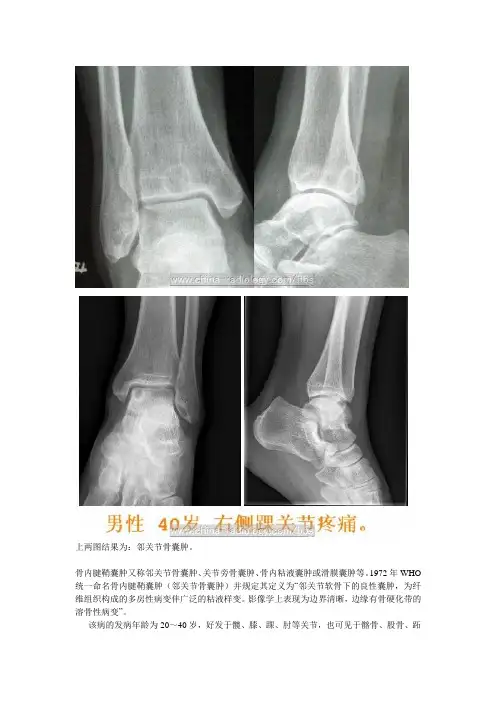

上两图结果为:邻关节骨囊肿。

骨内腱鞘囊肿又称邻关节骨囊肿、关节旁骨囊肿、骨内粘液囊肿或滑膜囊肿等。

1972年WHO 统一命名骨内腱鞘囊肿(邻关节骨囊肿)并规定其定义为“邻关节软骨下的良性囊肿,为纤维组织构成的多房性病变伴广泛的粘液样变。

影像学上表现为边界清晰,边缘有骨硬化带的溶骨性病变”。

该病的发病年龄为20~40岁,好发于髋、膝、踝、肘等关节,也可见于髂骨、股骨、跖骨、月骨、舟骨等处。

X线表现特点为:①病变邻近关节,位于长骨末端关节软骨下,呈偏心、圆形或椭圆形溶骨区。

②溶骨区有轻度膨胀,邻近骨皮质变薄,其中可见粗细不均的条状间隔。